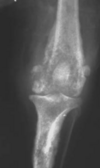

Left image: gunshot caused fracture.

Right image: osteosarcoma caused fracture.

identify

classic osteosarcoma CCLR secondary to neoplasia metastasis to lungs first (other intestinal organs also poss.) osteosarc. can have both new bone formation as well as lysis.